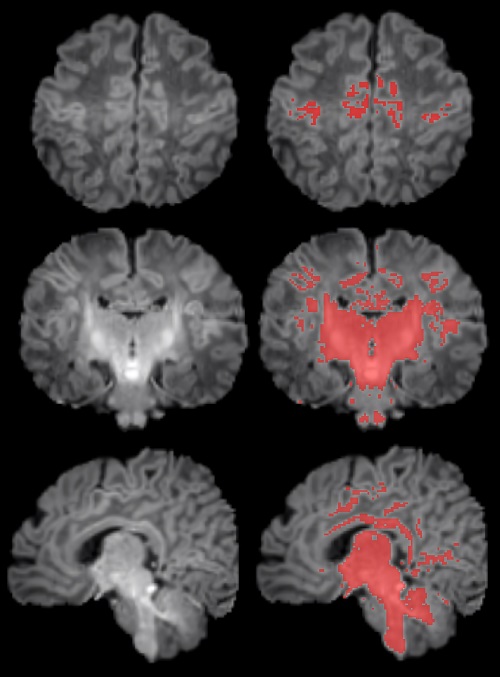

Il·lustració de les regions mielinitzades (en vermell) en el cervell del nadons

Per portar a terme l'estudi es van reclutar dones embarassades en seguiment a l'Hospital Clínic Barcelona, l'Hospital de Sant Pau i l'Hospital Sant Joan de Déu. Es van monitorar els nivells de contaminants atmosfèrics als quals estaven exposades durant la gestació i, després del part, es van seleccionar 132 nadons. A aquests se'ls va realitzar una ressonància magnètica abans de complir el primer mes de vida per observar el grau de maduració cerebral segons els seus nivells de mielinització.

Els resultats mostren una correlació clara entre una major exposició materna a PM2.5 durant l'embaràs i una menor mielinització en el cervell dels nadons. "La contaminació atmosfèrica, concretament les PM2.5, s'associa amb una alteració en el procés de mielinització, un mecanisme essencial de maduració cerebral. Per això cal continuar controlant la contaminació i estudiar com aquest alentiment pot influir en el desenvolupament posterior del cervell dels infants", expressa Martínez-Vilavella. El treball també indica que aquest efecte respon a la combinació dels diferents elements que formen les PM2.5, sense que se'n pugui identificar un d'únic com a responsable.